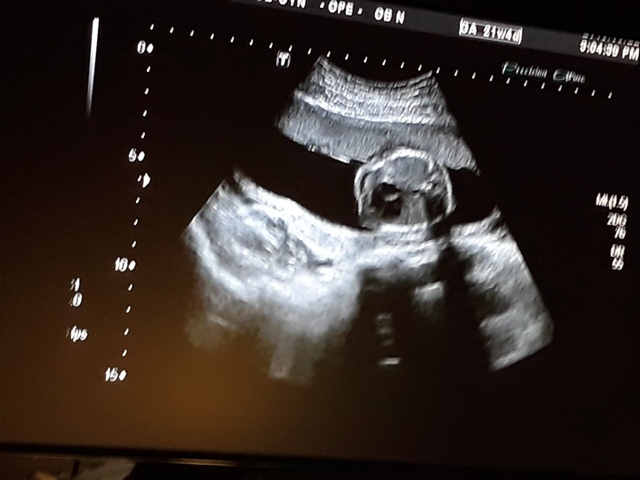

當小純進入診間看診時,我並沒有進去,因為小純說,有時男生不能進去,會被請出來。在外頭等待的我感到很緊張,不久之後,謢理人員請我進入診間,我嚇了一跳,想說發生什麼事了,進入之後,得知小純真的懷孕了,而且已懷了九星期又五天。看診的醫師說,驗孕棒第二條線淡淡的,沒想到胚胎照出來那麼大了,說Baby很健康。還說一閃一閃的是他的心跳,有頭、有手、有腳還有臍帶。小純後來說看了內心覺得很感動,才叫我一起進去看。

小純肚子裡的Baby超音波圖↓